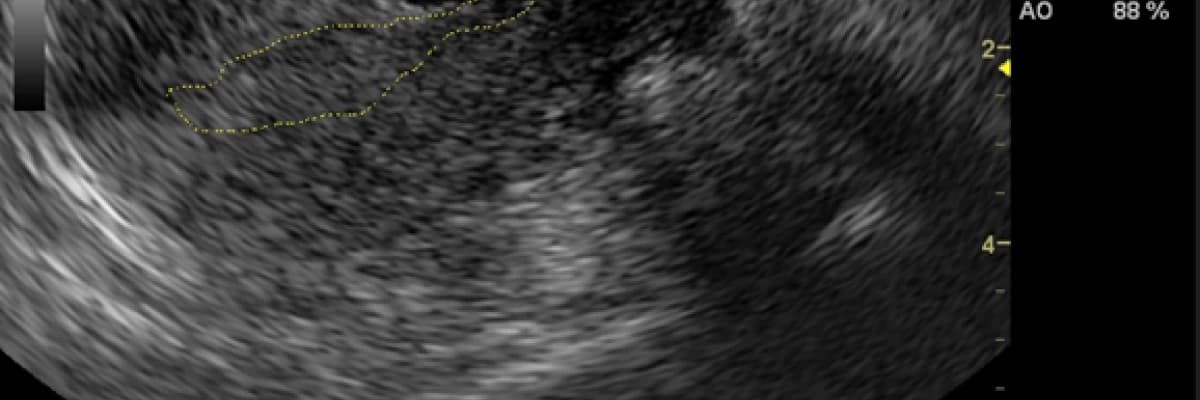

Sezaryen skar gebelikleri sezaryenlerin uzun süreli komplikasyonlarından biri olup sıklığı tüm gebelikler içinde %0,15’tir. Bu durum erken tanınmaz ve tedavi edilmezse hayatı tehdit eden sorunlara yol açabilmektedir. Sezaryen skar gebeliği gebelik büyüdükçe kontrol altına alınamayan yaşamı tehdit eden kanamalara, rahim yırtılmalarına neden olarak rahimin alınması ve gebelik kaybına yol açabilir. Ultrasonografi (USG) hastalığın tanısında gebeliğin ilk üç ayında önemli bir tanı aracıdır. Gebelik kesesi (GS) rahim kas tabakası ile mesane arasında izlenir. Hastanın başvuru şikâyetleri karın ağrısı ve/veya vajinal kanama olabileceği gibi hiçbir bulguda vermeyebilir ve olağan takipler sırasında fark edilir. Skar gebeliğinin servikal, servikoistmik gebelikler ve düşüklerden ayırıcı tanısının yapılması önemlidir

Transvajinal USG’de aşağıdaki kriterlerle tanı konulur.

Boş uterin kavite, endometriyum net olarak görülmeli,

Boş servikal kanal,

Rahimin usg görüntüsünde rahim ön duvarında alt segmentle mesane arasında sezaryen kesisine yerleşmiş gebelik kesesi görüntüsü